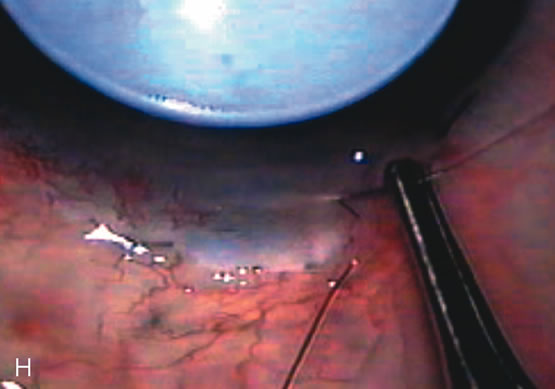

Fig. 7. Phacotrabeculectomy adjacent to a failed filter in cataractous eye. The ability to combine small-incision cataract extraction with trabeculectomy all through the same incision adjacent to the failed filter allows the surgeon to work in a familiar superior area. Avoiding incisions into the existing bleb decreases conjunctival buttonholes, hypotony, operating room time, and subconjunctival bleeding. A. Appearance of failed bleb with exposure of superior temporal quadrant gained with a corneal traction suture. B. Prepare a limbus-based conjunctival flap and a scleral flap. C. This bleb is at high risk to fail again justifying the need for MMC, 0.2 mg/cc applied on a pledget for 4 minutes. D. Insert the keratome and perform phacotrabeculectomy in the usual fashion.